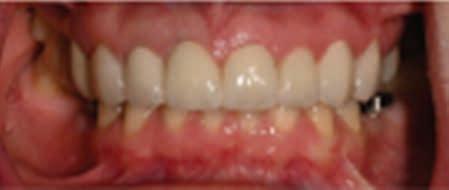

Intraoral assessment revealed that the maxillary left permanent central incisor was intruded 6-7 mm along with buccal displacement. No other extraoral, intraoral or dental injuries were noted. Intraoral radiographs taken confirmed the intrusive luxation injury. The permanent lateral incisors had erupted and the primary canines were not mobile. The initial clinical presentation of the child and associated radiograph are shown in Figure 1. Informed consent was obtained from the patient’s parents to initiate treatment.

Figure 1. Initial clinical presentation and radiograph of the child at approximately 30 minutes of the dental injury.

The patient returned for his routine preventive visit after two months. At this visit, the traumatized tooth was free of pain or discomfort, maintained a favorable position and did not exhibit any discoloration. Thermal testing was performed and all the maxillary permanent incisors responded comparably without any lingering sensitivity. The clinical picture and radiograph at this 2-month mark is shown in Figure 5.

Figure 5. Clinical picture and radiograph at two months after intrusion injury.